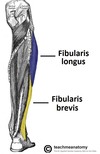

Identify the two muscles in the lateral compartment of the leg

- Fibularis longus

- Fibularis brevis

Describe the structure, function and innervation of the fibularis longus muscle

- Structure: larger and more superficial muscle within the compartment

- Function: plantarflexion, eversion, supports the lateral and transverse foot arches

- Innervation: Superficial fibular nerve

State the origin and attachment of the fibularis longus muscle

- Origin: superior and lateral surface of fibula and lateral tibial condyle (moves posterior to the lateral malleolus)

- Attachment: medial cuneiform and base of metatarsal I (crosses under foot)

Describe the structure, function and innervation of the fibularis brevis muscle

- Structure: deeper and shorter than fibularis longus

- Function: eversion

- Innervation: superficial fibular nerve

State the origin and attachment of the fibularis brevis muscle

- Origin: inferolateral surface of the fibular shaft (travels posteriorly to the lateral malleolus)

- Attachment: tubercle on metatarsal V (past over calcaneus and cuboid)